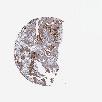

UROTHELIAL CANCER - Protein expressioni

A mouse-over function shows sample information and annotation data. Click on an image to view it in a full screen mode. Samples can be filtered based on level of antibody staining by selecting one or several of the following categories: high, medium, low and not detected. The assay and annotation is described here.

Note that samples used for immunohistochemistry by the Human Protein Atlas do not correspond to samples in the TCGA dataset.

Antibody stainingi

Antibody staining in the annotated cell types in the current human tissue is reported as not detected, low, medium, or high, based on conventional immunohistochemistry profiling in selected tissues. This score is based on the combination of the staining intensity and fraction of stained cells.

Each image is clickable and will lead to virtual microscopy that enables deeper exploration of all samples and also displays staining intensity scores, fraction scores and subcellular localization as well as patient and tissue information for each sample.

Antibody HPA000263

Antibody HPA000763

Antibody CAB037312

Staining

High

Medium

Low

Not detected

Intensity

Strong

Moderate

Weak

Negative

Quantity

>75%

75%-25%

<25%

None

Location

Nuclear

Cytoplasmic/membranous

Cytoplasmic/membranous,nuclear

Urothelial carcinoma, High grade

Urothelial carcinoma, Low grade